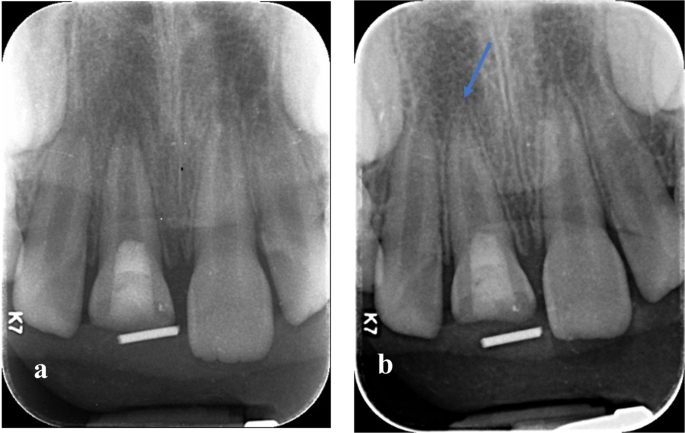

Continued root lengthening was observed in this study, the mean increase in root length in mm and percentage between 12 months follow-up and pre-operative root length in Group (N) was 1.03 (±ā0.97)āmm, 8.52(±ā3.33)% and in Group (W) was 1.04 (±ā0.86)āmm, 8.64(±ā4.30)% with no significant difference between both groups. Mean and Standard deviation (SD) values are shown in TableĀ 4. Digital radiographs showing an increase in root length in Group (N) and (W), Figs.Ā 7, 8.

a Baseline immediate post-operative radiograph showing the immature root of upper right central incisor. b 12 months follow-up radiograph showing the increase in root length in upper right central incisor.